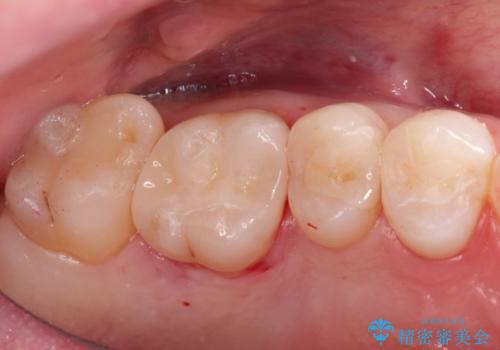

きれいな被せ物になり、患者さんにも満足していただけました。

歯牙の破折を防ぐために、セラミッククラウンにて修復しています。